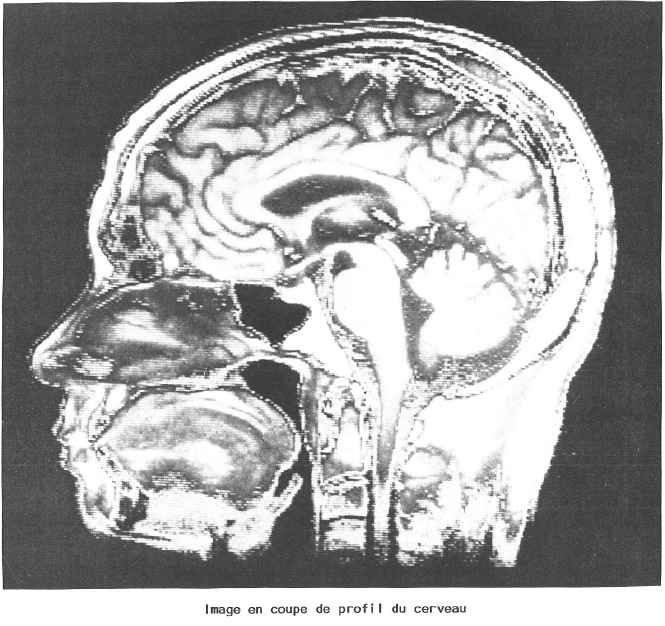

- par résonance magnétique nucléaire (R.M.N.).

Ces deux appareils donnent des images remarquables du cerveau.

L’I.R.M. (imagerie par résonance magnétique) est fondée sur l’étude du comportement du noyau d’un atome placé dans un champ magnétique intense et mis en résonance par une onde de radiofréquence émise par une antenne. Seuls certains atomes possèdent cette propriété de magnétisme nucléaire. Lorsque le corps n’est pas soumis à un fort champ magnétique, ses atomes d’hydrogène sont orientés de façon anarchique ; s’ils sont soumis à un champ magnétique intense, les protons s’orientent dans la direction du champ. Si dans cet état, on applique une onde de radio-fréquence, les atomes se mettent en résonance et un signal peut être enregistré. Si l’on supprime l’onde, les atomes vont revenir à leur état initial mais ce retour à l’équilibre se fait à des vitesses différentes selon la nature des tissus, en fonction de ce que les spécialistes appellent le temps de « relaxation ». Pour traiter ces informations, on a recours à l’ordinateur qui reconstruit une image à partir des mesures répétées. Le résultat final dépend de la concentration du noyau atomique employé (généralement l’hydrogène) et des temps de relaxation. Ainsi, ces derniers sont plus longs pour des tissus atteints de tumeurs, qu’elles soient bénignes ou malignes, que pour des tissus sains. L’intensité du signal est donc différente, ce qui permet de mettre en évidence les anomalies rencontrées.